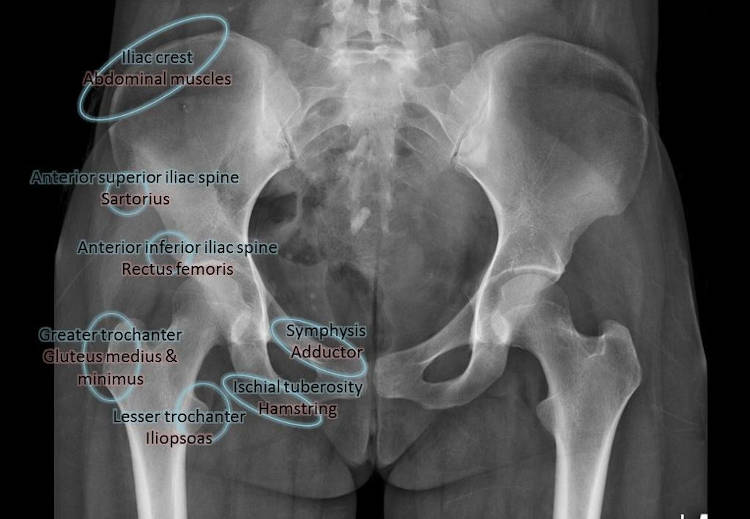

Στην περιοχή της λεκάνης συμπτωματολογία από υψηλή μυική φόρτιση εμφανίζεται περίπου στο 16ο -17ο έτος και αφορά συνήθως την πρόσθια άνω λαγόνια άκανθα – έκφυση του ραπτικού μυός, την πρόσθια κάτω λαγόνια άκανθα – ορθός μηριαίος και το ισχιακό όγκωμα (με συχνές αποσπάσεις στους ταχυδυναμικούς αθλητές) – οπίσθιοι μηριαίοι. Σημεία υψηλής μυικής τάσης και εμφάνισης άλγους εντοπίζονται επίσης: στον ελάσσονα τροχαντήρα – κατάφυση λαγονοψοίτη, στον μείζονα τροχαντήρα –στροφείς ισχίου και μέσος γλουτιαίος, λαγόνια ακρολοφία – κοιλιακοί, άνω γωνία ηβικής σύμφυσης – ορθός κοιλιακός. Η πολύπλοκη ανατομική της περιοχής της λεκάνης εγείρει διαγνωστικές αμφιβολίες πολλές φορές δυσεπίλυτες με τις απεικονιστικές προσεγγίσεις ανεπαρκείς (οστικά οιδήματα στις MRI, οιδήματα μαλακών μορίων στους υπερηχολογικούς ελέγχους).